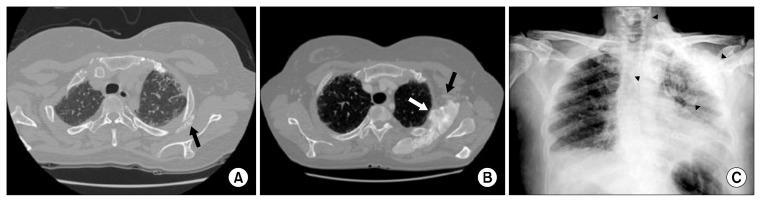

Extensive tumoral calcinosis affecting a large joint is uncommon in patients with systemic sclerosis. We report the case of a 52-year-old female patient referred for a growing calcified mass in the shoulder. She was diagnosed with interstitial lung disease and progressive systemic sclerosis. Although the pain and disability associated with the affected joint was not severe, the patient underwent surgical excision because the mass continued to grow and was likely to produce shoulder dysfunction and skin ulceration. The patient appeared well 10 months after surgery with no signs of recurrence. This report highlights the timing and indication of surgical excision in similar cases.